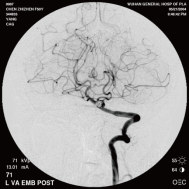

弹簧圈栓塞后造影示左椎动脉夹层动脉瘤消失, 左椎动脉、 多发动脉瘤夹闭术前、术中

左侧小脑后下动脉循环通畅